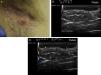

Hidradenitis suppurativa. A, Long erythematous lesion in the right armpit. The red circle shows the clinically evident area. The blue lines show the affected area as seen by ultrasound. B, Ultrasound image showing an underlying fistulous tract. C, Mild inflammatory activity evidenced by Doppler ultrasound.

Ultrasound Criteria for Elementary HS LesionsThe main ultrasound findings in HS include diffuse alteration of dermal echogenicity patterns, dermal thickening, dermal pseudocysts, widening of hair follicles, and identification of fluid collections and fistulous tracts (Figs. 3–5).83

The ultrasound findings corresponding to the different stages of clinical disease progression are described below. The earliest finding is hair follicle widening, which appears to have a key role in the development of HS.

The next stage consists of alteration of the dermal pattern (first perifollicular and then diffuse) and dermal thickening, which reflects the marked underlying inflammatory process, largely brought about by the action of varying innate immune system mediators. Accordingly, both degree of hypoechogenicity and the extent of the hypoechogenic area can provide important clues regarding the degree of underlying inflammation (Figs. 3–5).83

Patients with high inflammatory burden will have dermal pseudocysts (Fig. 3 A and B), which appear on ultrasound as round or oval hypoechoic or anechoic nodular structures. The next stage involves the development of fluid collections, which are seen on ultrasound as hypoechoic or anechoic fluid deposits in the dermis or hypodermis that are typically connected to the base of the altered hair follicle (Fig. 4 A-C).

The final stage is the development of fistulous tracts, seen as bands of hypoechoic or anechoic structures crossing through different structures located in the different layers of the dermis or hypodermis, and connected to the base of altered follicular structures (Fig. 5 A-C).